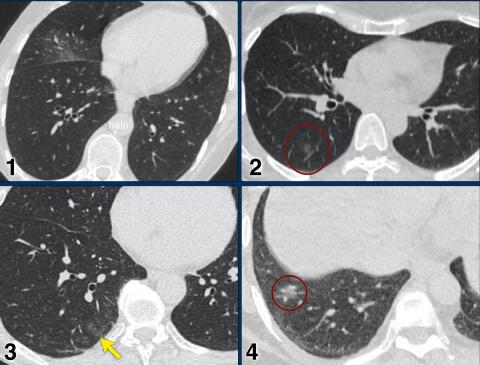

CO-RADS _____ (RTPCR confirmed)

CO-RADS _____ (very high level of suspicion for pulmonary involvement by COVID-19 based on typical CT findings)